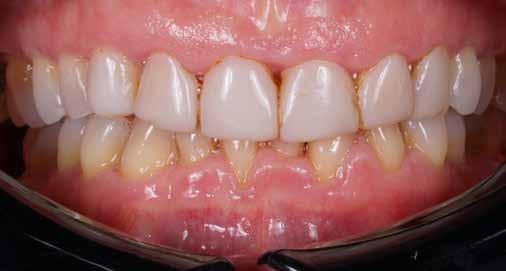

A felső frontfogak állapota elhanyagolt, a parodontális struktúrák részben erősen károsodottak, VMK korona az 12 zónában, az ínyszél szürke, fekete approximális háromszögek… vörös-fehér esztétikáról nem is beszélhetünk (1. kép). Így jelentkezett a hölgypáciens a Weston Dental Specialists Group rendelőben. Elvárásai magasak voltak. A defektusok kezelését, a gingiva lefutásának korrigálását kívánta. Gyorsan világossá vált, hogy a megoldást csak a négy frontfog teljes kerámiakoronával való ellátása jelentheti. A jelen eset bemutatja, hogy az IPS e.max ZirCAD Prime segítségével hogyan lehet tiszta, tetszetős és esztétikus mosolyt létrehozni.

1. kép: Kiindulási helyzet.